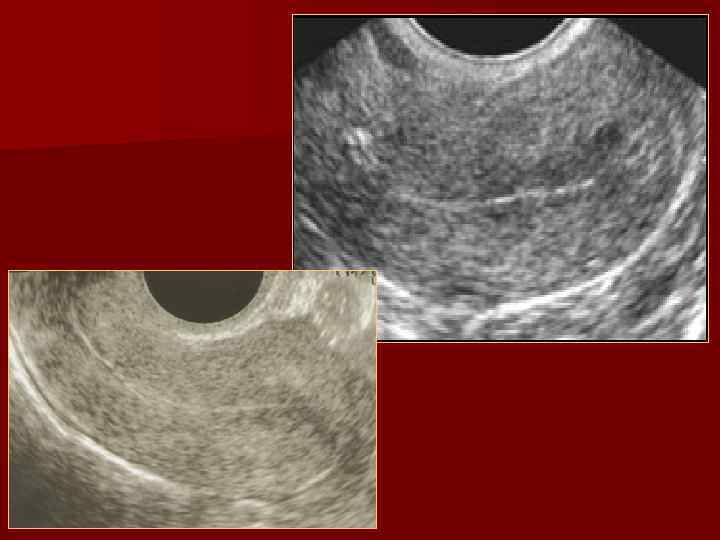

Вторая фаза менструального цикла Влияние прогестинов n Эндометрий гиперэхогенный n К 24 -27 дню толщина эндометрия постепенно снижается до 12 мм n

16 -18 день МЦ 20 -25 день МЦ